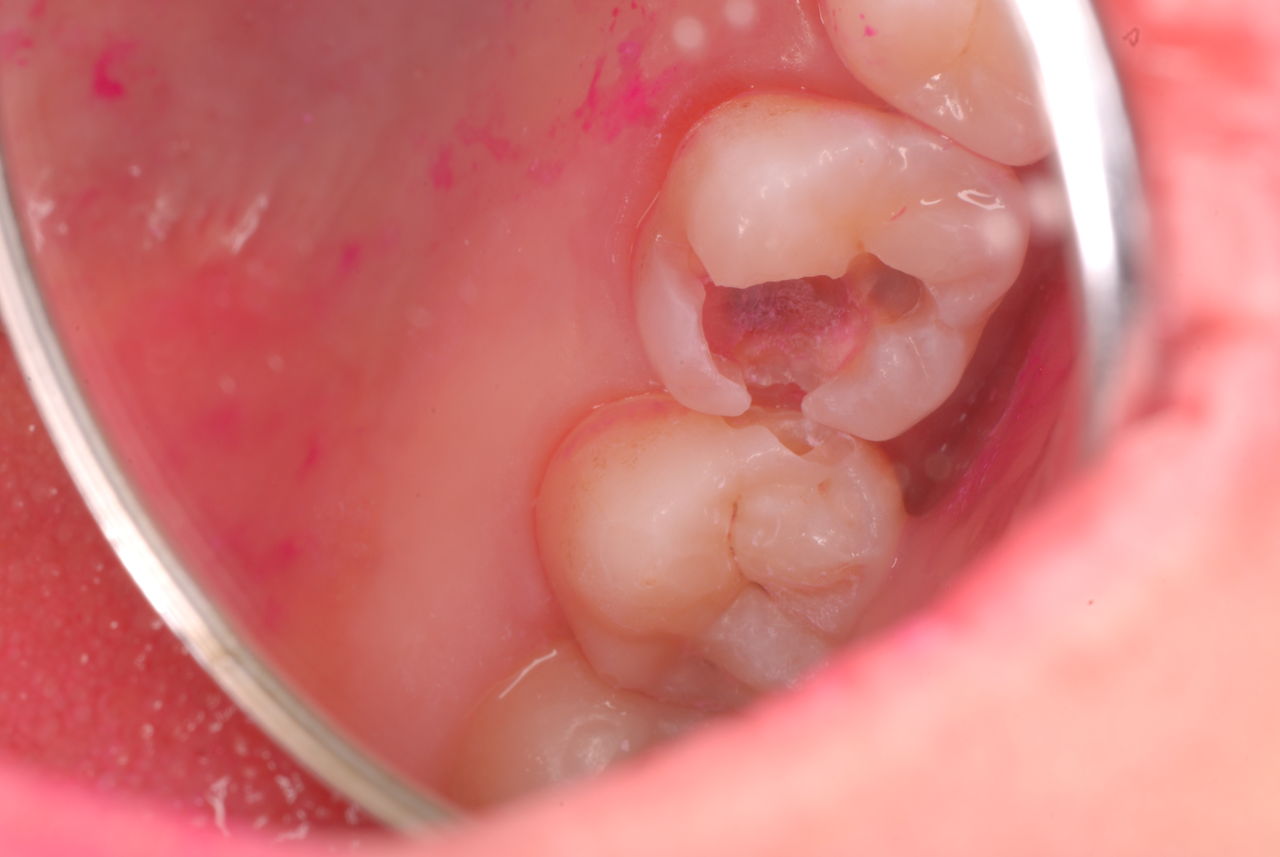

入れ歯の話から入りました。色々不満で注文があるようです。でも話が一段落して口腔内を調べると殆どの歯が重症で抜けそうな歯だらけなのです。

なぜ病気になるのかわからない方が多すぎます。歯が抜けるのは病気だからです。病気を治さずに何かお口の中に入れても土台である歯が抜けてしまっては同じことなのです。

何故歯が悪くなるのか、歯周病で抜けるのか分からなければ何を入れても歯は悪くなり抜けていくのです。

病気を治しましょう。それから差し歯や入れ歯を入れましょう!物を入れれば入れるほど、磨き方や掃除の仕方が上手にならなければ、すぐ抜けてくるのです。